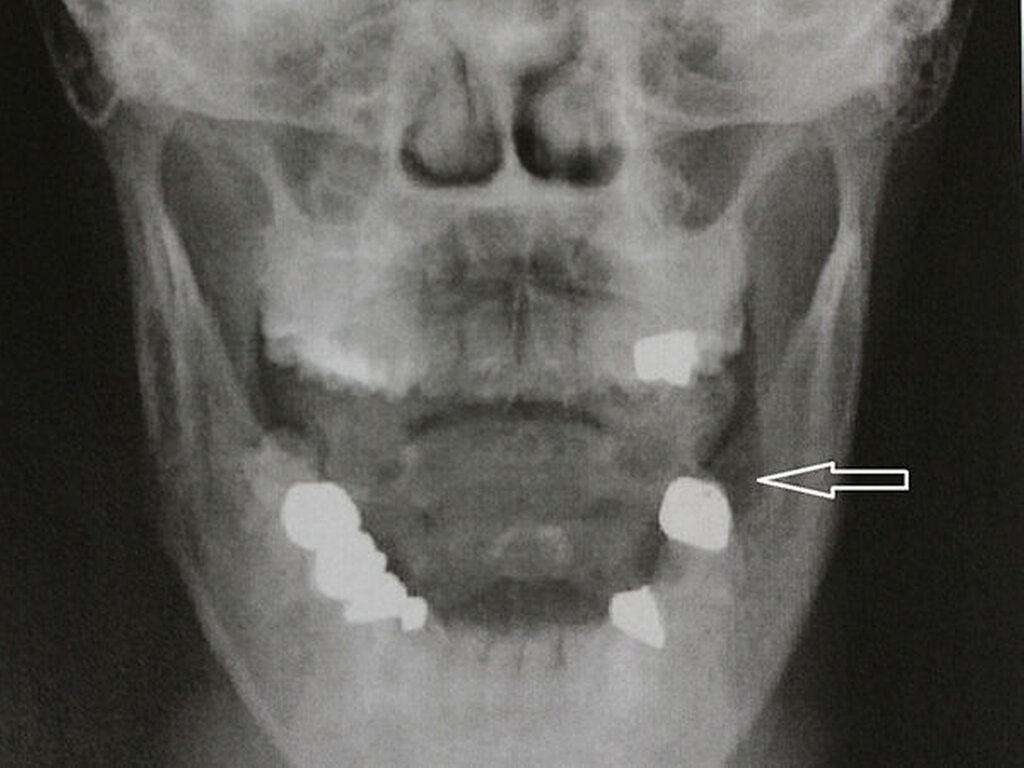

In der alio loco durchgeführten OPG-Aufnahme ergaben bei schlechter Aufnahmequalität ein allenfalls geringes sklerotisches Areal regio 036 sowie eine leichte apikale Aufhellung am Zahn 37. In der Clementschitsch-Aufnahme (Abbildung 1) zeigte sich eine - im Vergleich zur Gegenseite - leicht osteolytische Zone regio 038.

Die Patientin wurde daraufhin bei Verdacht auf eine Unterkiefer-Osteomyelitis stationär aufgenommen. In der Labordiagnostik fand sich ein gering erhöhtes CRP von 1,1 mg/dl (Referenz <0,5 mg/dl) bei normwertigen Leukozyten (7,3 /nl) und bei ansonsten unauffälligen Routine-Parametern. In der durchgeführten CT zeigte sich eine unscharfe, runde Osteolyse regio 038 mit periostaler Reaktion (Abbildung 2).